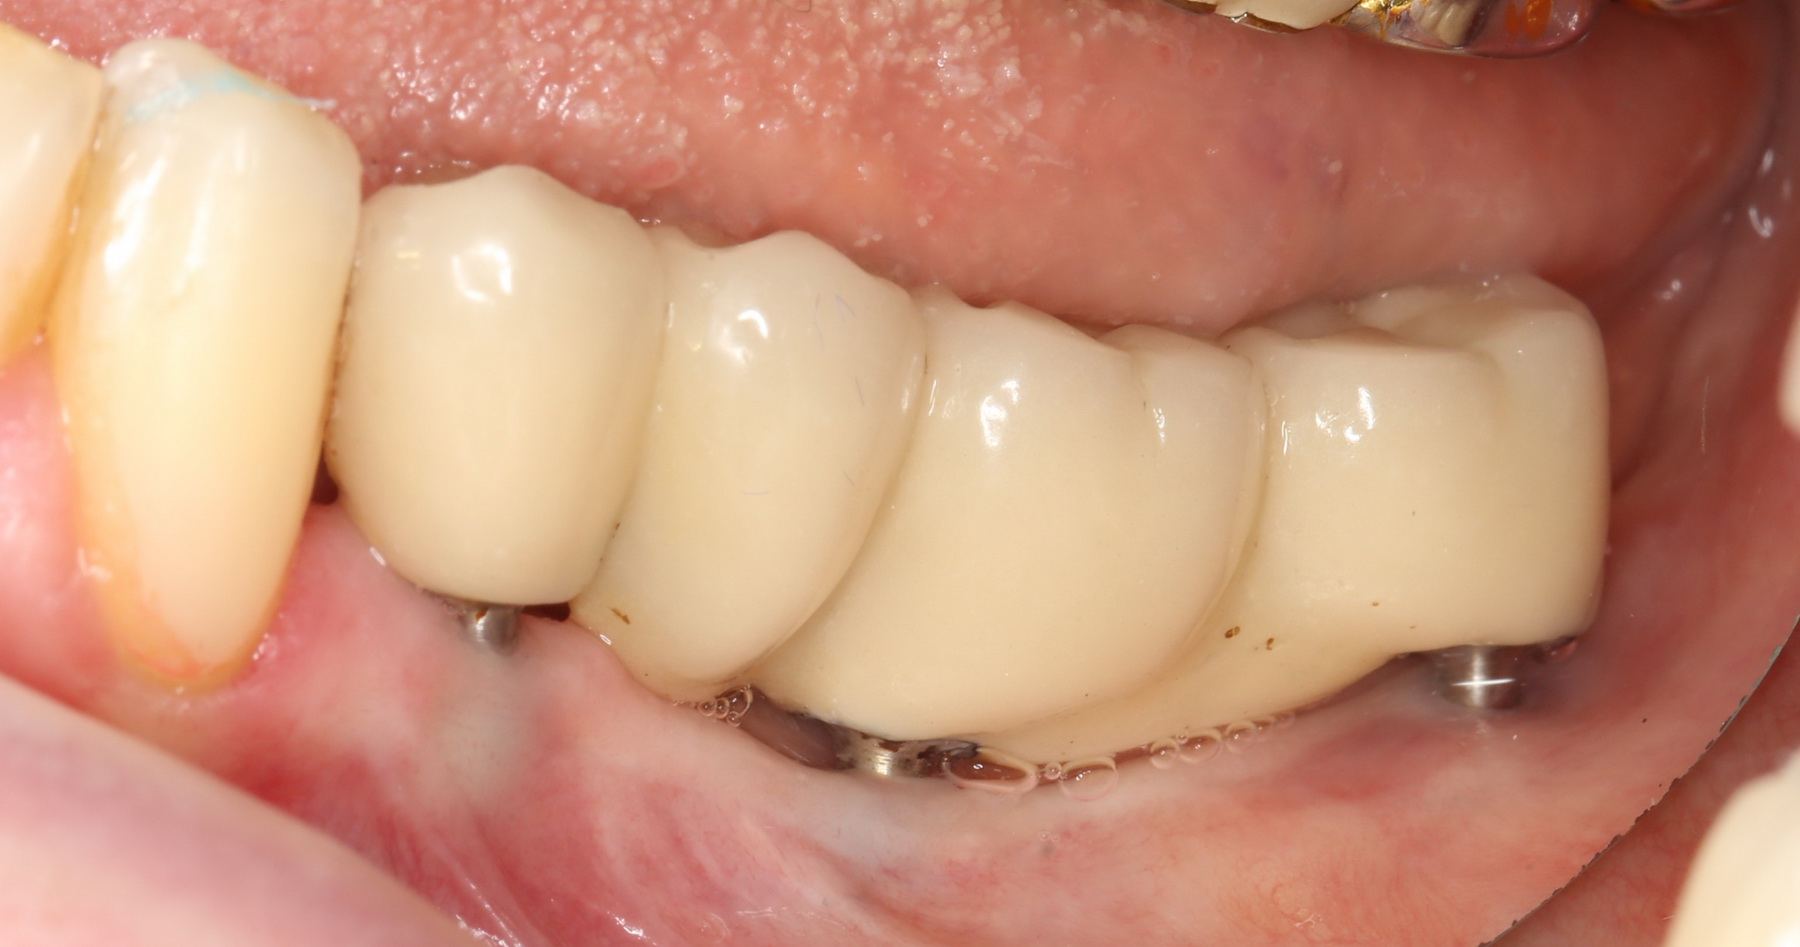

и, периодически, мне приходится видеть пациентов с базальными имплантами:

Как правило, вся работа с этими имплантами сводится к их удалению:

Нижние, вроде как, вполне держатся, на них стоят постоянные металлокерамические коронки. Помните, что я говорил про один из главных критериев качественной имплантологической работы? Состояние десны вокруг имплантов!

Хотите на это посмотреть? Этого не покажут, рекламируя базальную имплантацию:

То есть, друзья, десны нет. За подобную работу в наших клиниках рвут диплом в клочья и выгоняют нафиг. Для базальной имплантации, такая ситуация — норма:

И теперь представьте, как за всем этим ухаживать? Как этим жевать, если учесть тот факт, что ножка импланта, торчащая из десны, легко гнется? И сколько такие импланты вообще прослужат, если учесть сложную гигиену и неудобную форму протеза в этом участке?